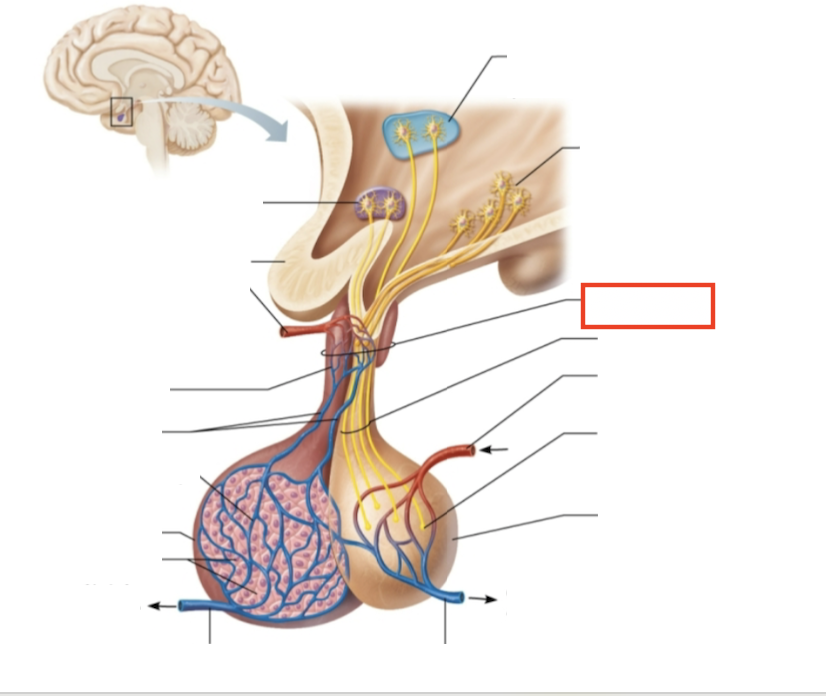

What structure is highlighted?

hypothalamic neurons in the paraventricular nuclei

What structure is highlighted?

neurons in the ventral hypothalamus

What structure is highlighted?

infundibulum (connecting stalk)

What structure is highlighted?

hypothalamic-hypophyseal tract

What structure is highlighted?

inferior hypophyseal artery

What structure is highlighted?

neurohypophysis (storage area for hypothalamic hormones)

What structure is highlighted?

posterior pituitary

What molecules are produced here?

oxytocin, ADH

What structure is highlighted?

venule

What structure is highlighted?

venule

What molecules are produced here?

TSH, FSH, LH, ACTH, GH, PRL

What structure is highlighted?

secretory cells of adenohypophysis

What structure is highlighted?

anterior pituitary

What structure is highlighted?

secondary capillary plexus

What structure is highlighted?

hypophyseal portal veins

What structure is highlighted?

primary capillary plexus

What structure is highlighted?

superior hypophyseal artery

What structure is highlighted?

superior hypophyseal artery

What structure is highlighted?

optic chiasma

What structure is highlighted?

hypothalamic neurons in the supraoptic nuclei